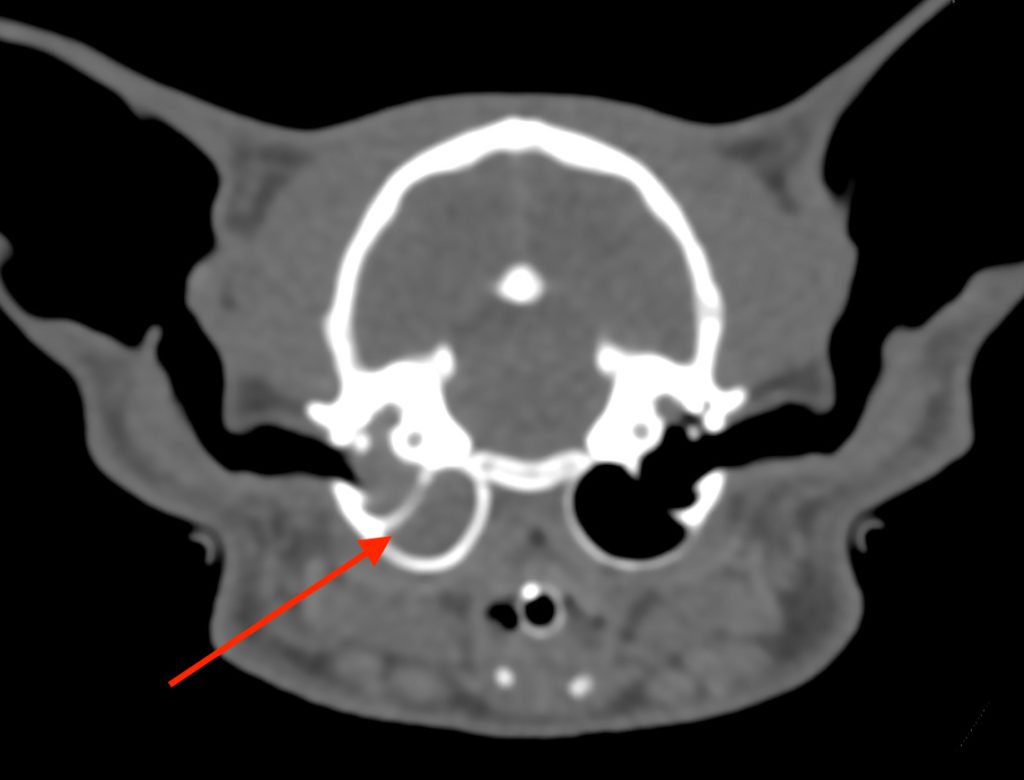

なお、偶然見つかった所見ではありますが、左耳の奥の鼓室胞という空間に、貯留物が認められました。

これは中耳炎が疑われる所見ですが、鼻炎に伴い液体貯留が見られたり、

全くの無症状で液体貯留が見られたりすることがあります。

本症例でも中耳炎に関連する症状が認められませんでしたので、慢性鼻炎の治療をしながら経過観察としました。